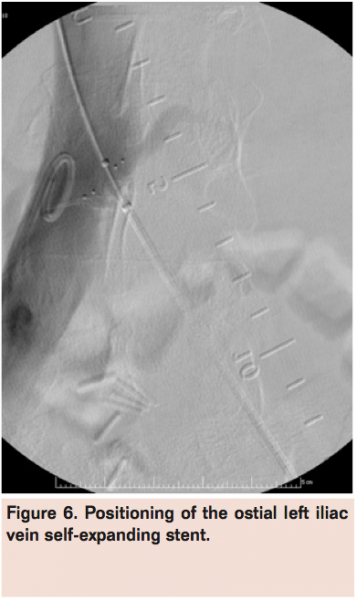

A Wildcat chronic total occlusion catheter (Avinger) was advanced in active and passive modes to traverse the occlusion (Figure 4) followed by a glidewire (Terumo) with confirmation of intraluminal position within the IVC via contrast injection (Figure 5). Serial balloon venoplasty was performed in ascending fashion using EverCross 6 mm x 100 mm, 7 mm x 120 mm, and 12 mm x 60 mm balloons (Covidien) and subsequent stenting with Protégé Everflex 12 mm x 80 mm and 8 mm x 150 mm self-expanding stents (Covidien) in overlapping fashion from the ostium of the left common iliac vein (Figure 6) to the common femoral vein. The entire stented segment was post-dilated with the EverCross 12 mm x 60 mm balloon and final venography demonstrated brisk flow through the left common femoral to common iliac vein stent (Figure 7).